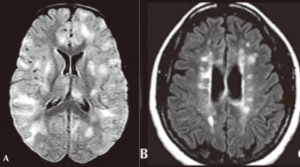

Neuroimaging is helpful in diagnosing ADEM. At presentation, MRI findings may be similar between MS and ADEM. In patients with ADEM, T2-weighted and fluid attenuated inversion recovery (FLAIR) brain MRI typically shows large, bilateral, hyperintense, lesions (>1-2 cm) that are diffuse and poorly demarcated.[22] ADEM lesions can involve both the white and gray matter, affecting the subcortical and central white matter, cortical gray-white matter junction, and deep gray matter of the basal ganglia, thalami, cerebellum, brainstem, with very rare T1 hypointense “black hole” white matter lesions that are more typically seen in MS.[14][22] Gadolinium enhancement of ADEM lesions is found in only 30% of cases.[35]

Key brain MRI features found in ADEM that are absent in MS include periventricular sparing without Dawson fingers (ovoid lesions perpendicular to lateral ventricles), both deep gray matter and cortical involvement, bilateral and diffuse lesions that are large, globular, and poorly demarcated.[22] In 1/3 of cases, spinal cord demyelination is seen over multiple segments. Diffusion-weighted imaging (DWI) can help elucidate the timing of the demyelinating event.[39] In the first week following ADEM onset, DWI will show decreased diffusivity. This is thought to be a result of inflammation causing myelin sheath edema and accumulation of inflammatory cells, impeding the migration of water molecules. After the first week, the extracellular space widens, causing increased water diffusivity on DWI.[39]